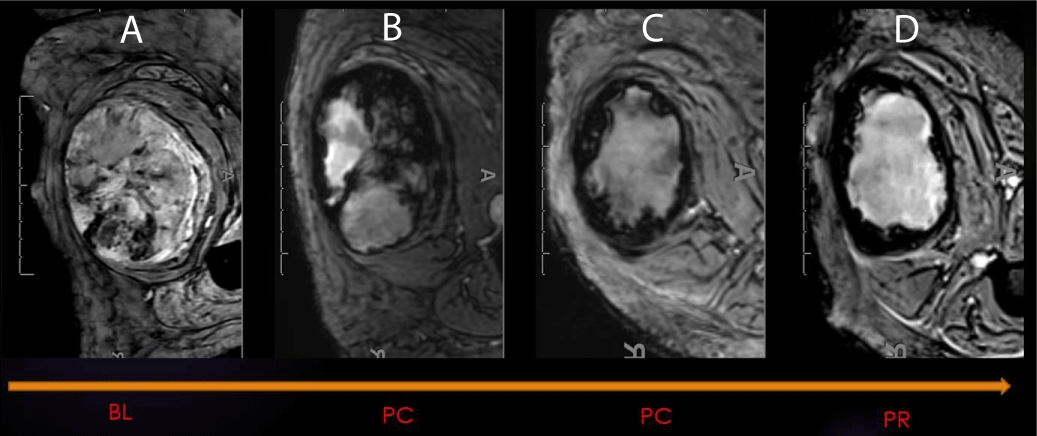

Diffusion-weighted imaging (DWI) is an MRI sequence that measures the density of tumor cells. DWI uses the movement of water molecules to determine the cellularity of malignancies, which have fewer extracellular spaces and smaller cytoplasm than normal tissues. The restricted diffusion in malignancies results in lower ADC values, which can help distinguish them from benign lesions (Figure 2). Effective therapy resulting in cell death increases water diffusion, reflected in higher ADC values. ADC values are inversely correlated with the Ki67 labeling index, indicating a lower mean in higher proliferation groups [8,9]. DWI has also been shown to be a valuable biomarker for response assessment in sarcoma patients treated with preoperative radiation therapy. Changes at the cellular level occur before morphologic changes, making DWI a potential prognostic tool if performed early in treatment [10-14]. Not only ADC mean but also minimum ADC values are considerably higher in good responders (> 90% of necrosis by histological examination) than in poor responders [12].

Figure 2: ADC of Cellular STS - High-grade UPS: (A) DWI b800 demonstrating high signal intensity within the posterior left ankle tumor. (B) ADC map displaying a value of 0.8 x 10-3 mm2/s. This value is within the accepted range of restricted diffusion for cellular soft tissue sarcoma (0.7-1.1 x 10-3 mm2/s) (C-D) Intensity histogram curve demonstrates low ADC with Positive Skew (left-sided intensity histogram curve).

In our experience, good responders tend to have a lower baseline ADC mean and the highest percentage of increase at post-radiation MRI, often in the range of 40% [13] (Figure 3).